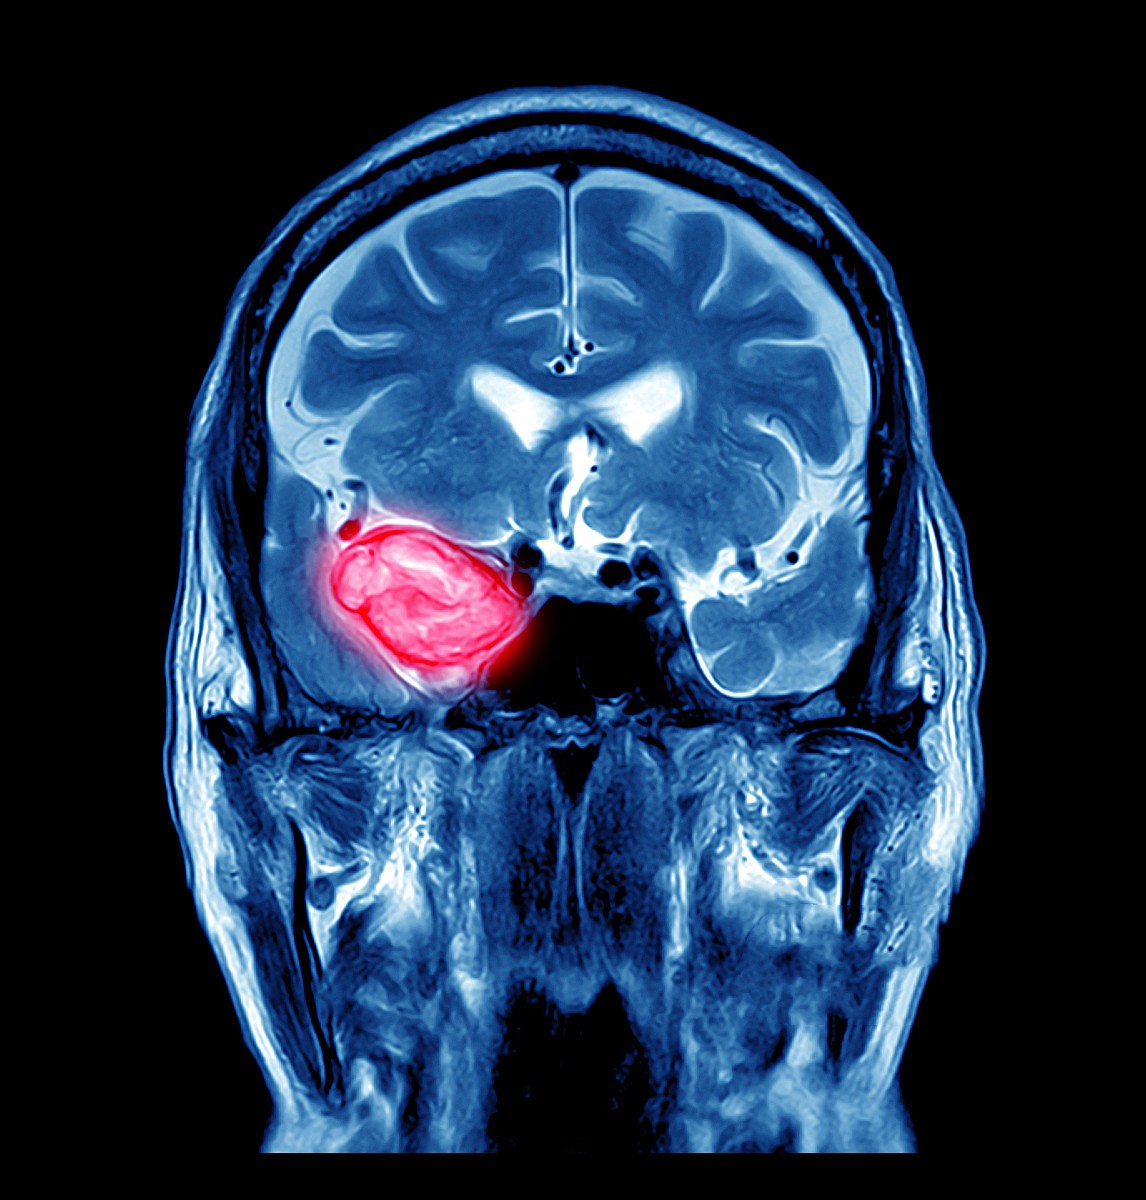

脑动脉瘤是指脑动脉内腔的局限性异常扩张(脑底动脉环,大脑中动脉分叉处,颈内动脉系统为多发部位)造成动脉壁的一种瘤状突出。脑动脉瘤未破裂时,患者基本上没什么症状,部分患者会有头疼,看东西模糊看不清有重影,侧脸麻木等;当脑动脉瘤破裂并出血时,患者可能会突然间头痛,意识模糊不清,看不清东西严重者甚至会失明,癫痫,眼睑下垂,此时就要去医院就医,以免造成终生残疾或危及生命。

又叫做磁共振血管造影,失败利用电磁波产生身体二维或三维结构图像。经常用于脑肿瘤的筛选,对于不适合用碘的患者,可以采用这个方式检查。